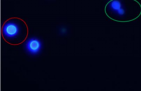

利用荧光染料特异性结合真菌细胞壁中的几丁质、β-葡聚糖等成分,在荧光显微镜下可呈现鲜明的荧光色,显著提升识别度。念珠菌、隐球菌、毛霉菌、曲霉菌等均可很好着色,且孢子、菌丝结构清晰可见。

曲霉菌 毛霉菌 隐球菌 念珠菌